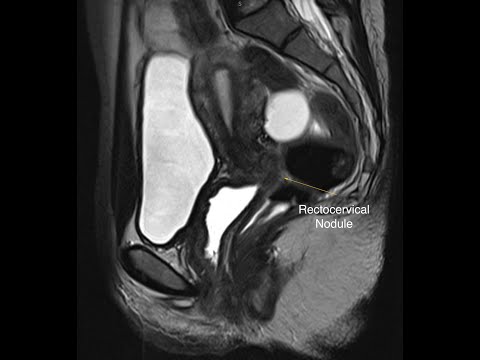

Hellow guys, Welcome to my website, and you are watching Anatomy, Utero-sacral Ligament Neurectomy (Frankenhauser), 36s. and this vIdeo is uploaded by Alysson Zanatta at 2016-10-09T00:42:30-07:00. We are pramote this video only for entertainment and educational perpose only. So, I hop you like our website.